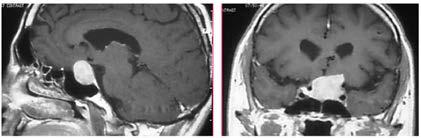

Issuu converts static files into: digital portfolios, online yearbooks, online catalogs, digital photo albums and more. Sign up and create your flipbook.